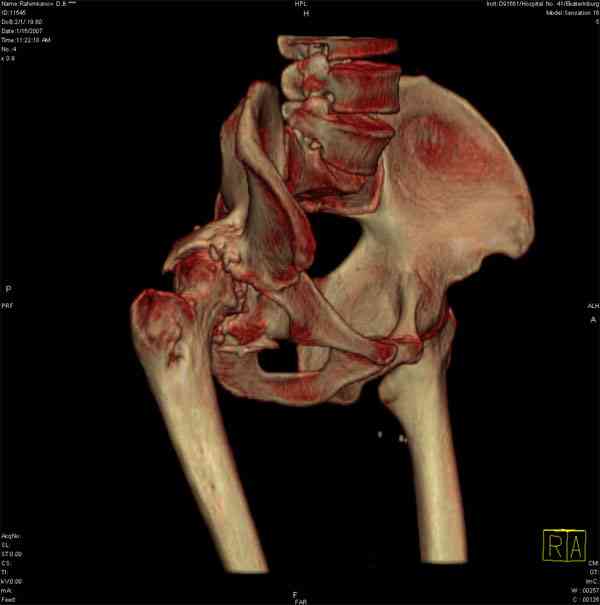

Еще одно наблюдение, неправильно сросшийся перелом заднего отдела ВВ с ввихом головки бедра 16-и летней давности.

С уважением, Р.Тихилов